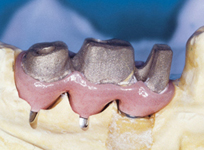

V případě chybění většího počtu zubů v postranních úsecích čelistí je možné ošetření pomocí implantátů, které nahradí ošetření pomocí snímacích náhrad kotvených na zbývajících zubech nebo patře.

Podmínkou je opět dostatečné množství kosti.

Protetické řešení může být pomocí můstku, který je kotvený na implantátech nebo pomocí jednotlivých korunek na implantátech.

V zásadě je možné do těchto můstků zařadit i přirozené zuby, zejména pokud je potřeba tyto zuby ošetřit proteticky – korunkami. Korunky nebo můstky mohou být na implantáty nacementovány nebo přišroubovány.

Zdravé zuby zůstanou zachovány a přitom náhrady jsou pevné, jako na vlastních zubech